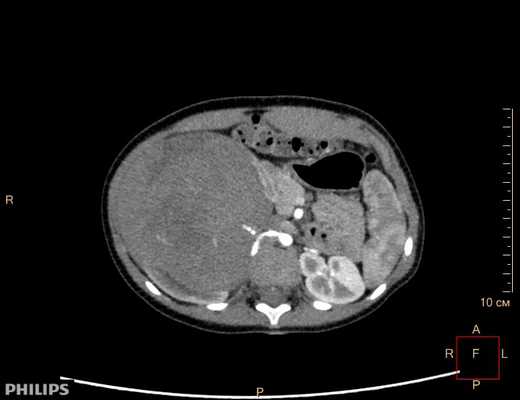

Компьютерная томография более детально дает информацию об анатомическом отношении опухоли к окружающим тканям и органам, позволяет оценить структуру опухоли (рис. 5).

Рис. 5. КТ нейрогенного образования забрюшинного пространства справа